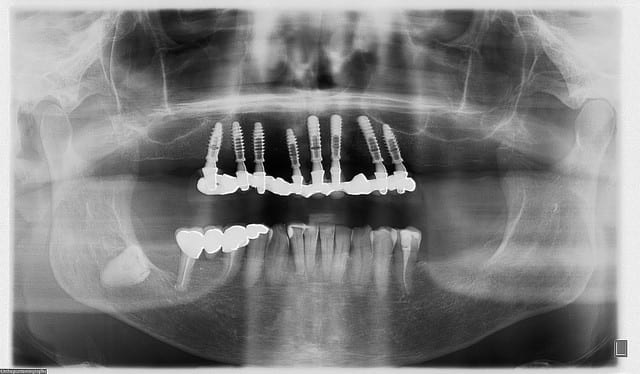

Pour illustrer mes propos sur la mise en charge immédiate, je vous joins une planche de photos.

C’est un cas d’extraction implantation et mise en charge immédiate. Le bridge provisoire est en résine sur une armature métal rigide. Cette armature à un rôle de fixateur externe qui réparti les contraintes sur tous les implants. Nous obtenons ainsi une stimulation intra-osseuse favorable à la cicatrisation de cette zone. Après 1 an de port, le cosmétique enregistreras les pistes d’occlusions, cette information est importante pour la réalisation du bridge d’usage.

La prothèse transitoire esthético-fonctionnelle posée en continuité de l’intervention à aussi une fonction de conformateur des tissus mous.

C’est une chirurgie guidée avec le dispositif POSITDENTAL.